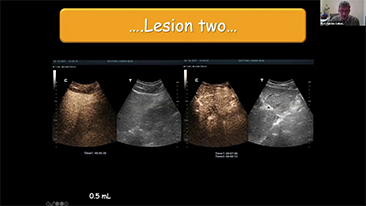

Diagnostisch ultrasoundsysteem

Een echografiesysteem voor algemene beeldvorming met volledig innovatieve functies van binnenuit. Alle innovaties zijn ontwikkeld op basis van diepgaande inzichten in complexe klinische scenario's en bieden nauwkeurige en tijdige antwoorden, evenals een uitstekende efficiëntie en opmerkelijke gebruikerservaring.